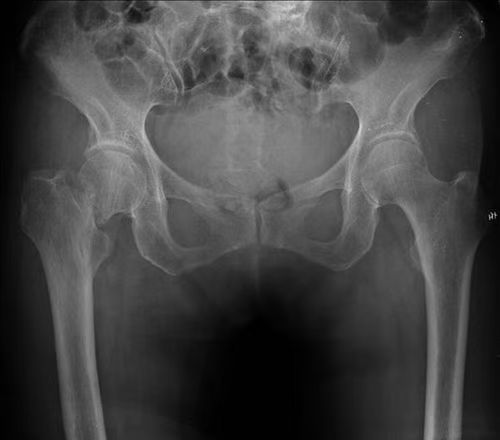

髋部骨折:包括股骨颈骨折及股骨粗隆间骨折,髋部的股骨颈是连接大腿骨和骨盆的关键部位,骨质会随着年龄增长而逐渐疏松,即使轻微滑倒碰撞也可能引发骨折。